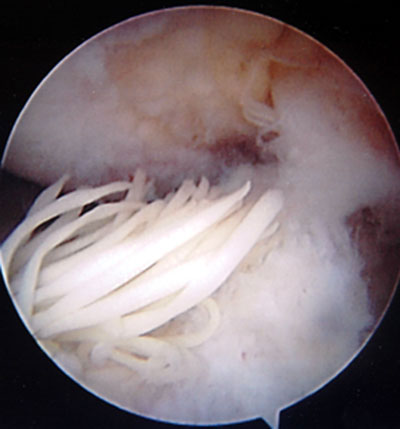

Imiddels is bij kunststof materialen (Dacron, polyester, Goretex e.d.) aangetoond dat deze structuren niet langdurig functioneren en uiteindelijk in een groot percentage falen. Op de foto zijn de restanten te zien van een opnieuw gescheurde kunststof kruisband ook wel xenograft genoemd. Kunststof materialen worden in Nederland dan ook niet meer gebruikt.